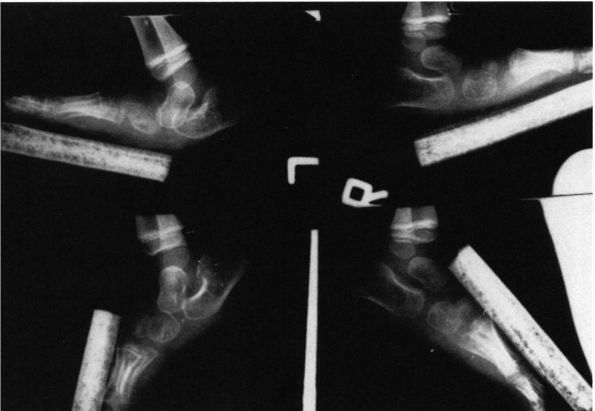

FIGURE 20-13.

Congenital vertical talus of left foot. (Hypermobile flatfoot with contracted Achilles tendon on the right foot.) In the simulated weight-bearing views (upper left and upper right), both feet have the evidence of a rocker-bottom deformity with dorsiflexion occurring at the midfoot, the hindfoot is in equinus, and the forefoot is in dorsiflexion. The talus is more severely plantar flexed on the left than the right. Both calcanea are in equinus, and on the left foot there is disruption of the calcaneal cuboid joint. On the plantar flexion views (bottom), note on the right side the longitudinal axis of the talus is collinear with the forefoot; but on the left (side with congenital vertical talus), the longitudinal axis of the talus is not collinear with the longitudinal axis of the metatarsals, indicative of the rigid nature of the deformity. |